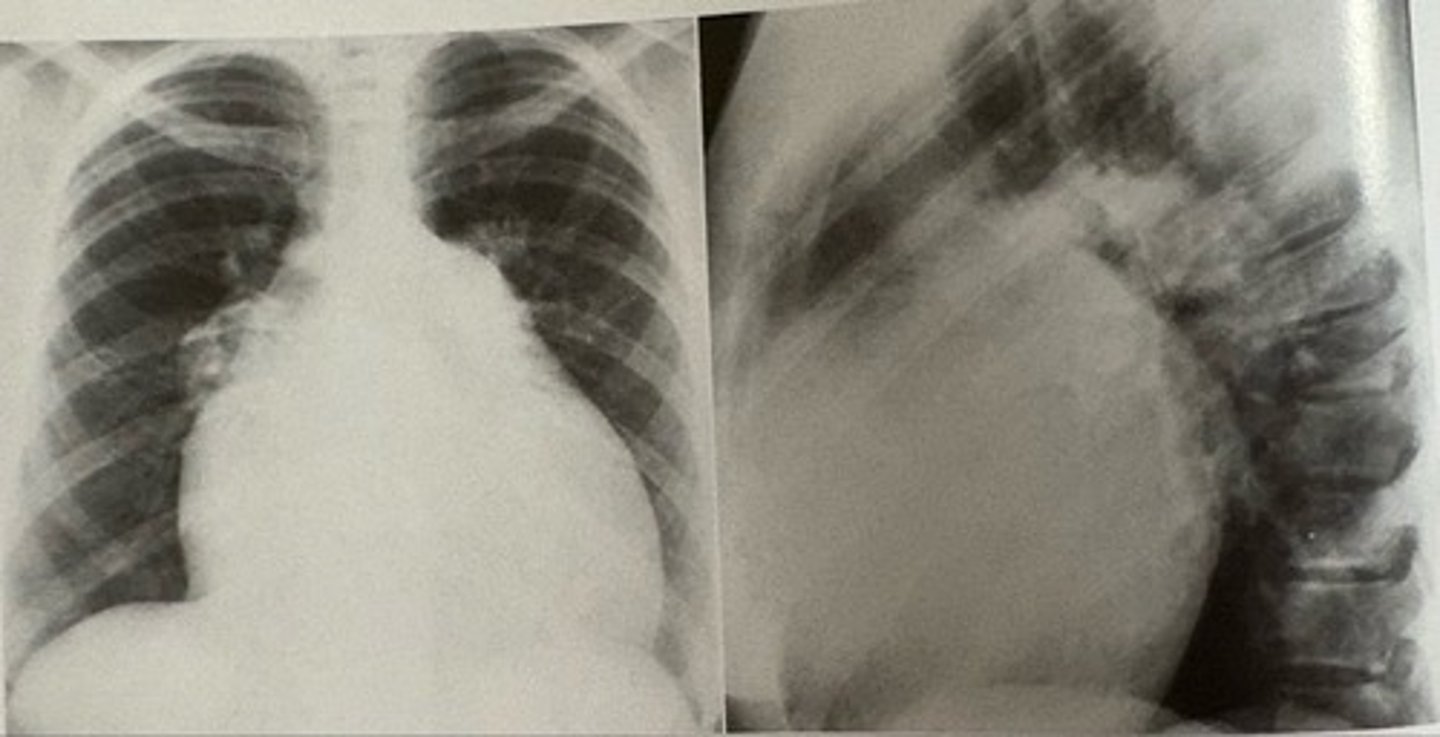

mitral stenosis

what pathology is present?